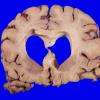

11B1 Pick Dz & ADNC (Case 11)_1

11B2 Pick Dz & ADNC (Case 11)_2

11B3 Pick Dz & ADNC (Case 11)_3

11B4 Pick Dz & ADNC (Case 11)_4

11B5 Pick Dz & ADNC (Case 11)_5

11B6 Pick Dz & ADNC (Case 11)_7

11B7 Pick Dz & ADNC (Case 11)_9

11B8 Pick Dz & ADNC (Case 11)_14